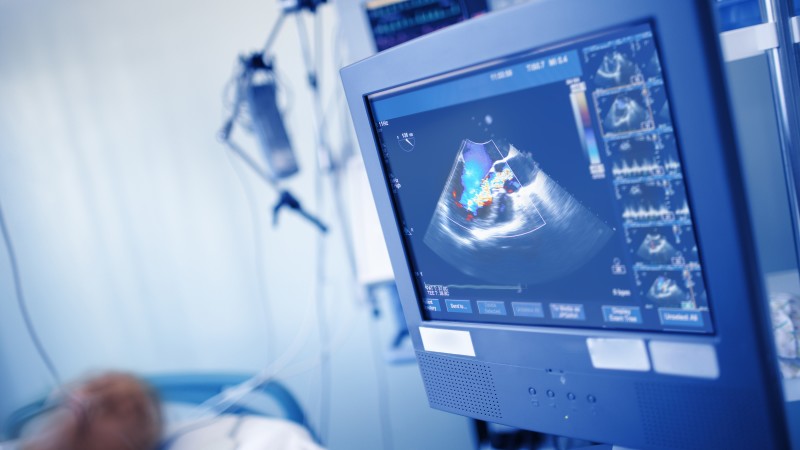

Early recognition and assessment of residual cardiac disease is important in those with COVID-19, according to an article published in Expert Review of Cardiovascular Therapy. These steps help facilitate disease-modifying treatments for subclinical damage that prevent or mitigate the pathogenesis of heart failure. Nevertheless, ECG and echocardiography usually detect only advanced stages of heart damage, when left ventricular function presents.

The authors recommended using cardiovascular magnetic resonance (CMR) for in-depth tissue characterization and identification of pathology of the myocardium, such as inflammation, edema, ischemia, and fibrosis.